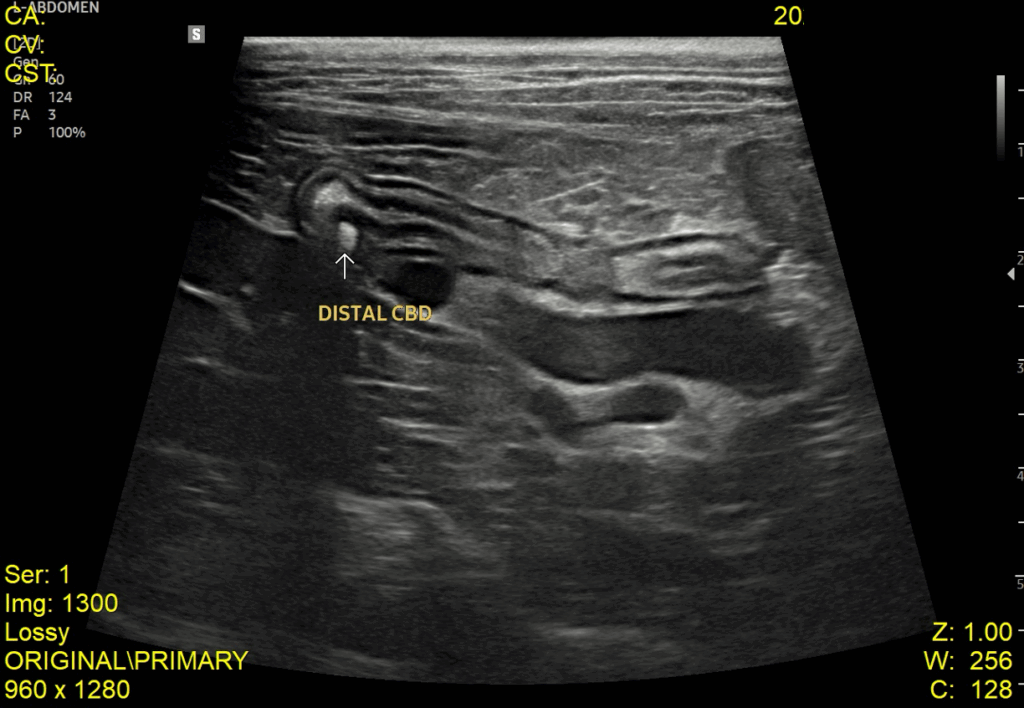

이어서 진행한 복부 초음파 검사에서는 췌장염 소견과 함께 위벽 및 일부 장 근층 비후가 관찰되었고, 담낭관(Cystic duct)과 총담관(CBD)이 심하게 확장되어 있으며 내강 내 슬러지가 확인되었습니다. 또한 담낭 내에는 중등도의 슬러지와 담석이 있었고, 간 내 담도 결석과 전반적인 간 에코 증가도 함께 확인되었습니다.

내원당시 복부초음파 검사 결과 / 출처: 강서YD동물의료센터